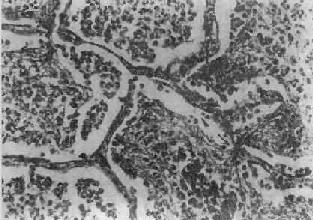

图9-13 全腺泡型肺气肿

末梢呼吸道弥漫性扩张,呈小囊状遍布于肺小叶内(径>200μm)